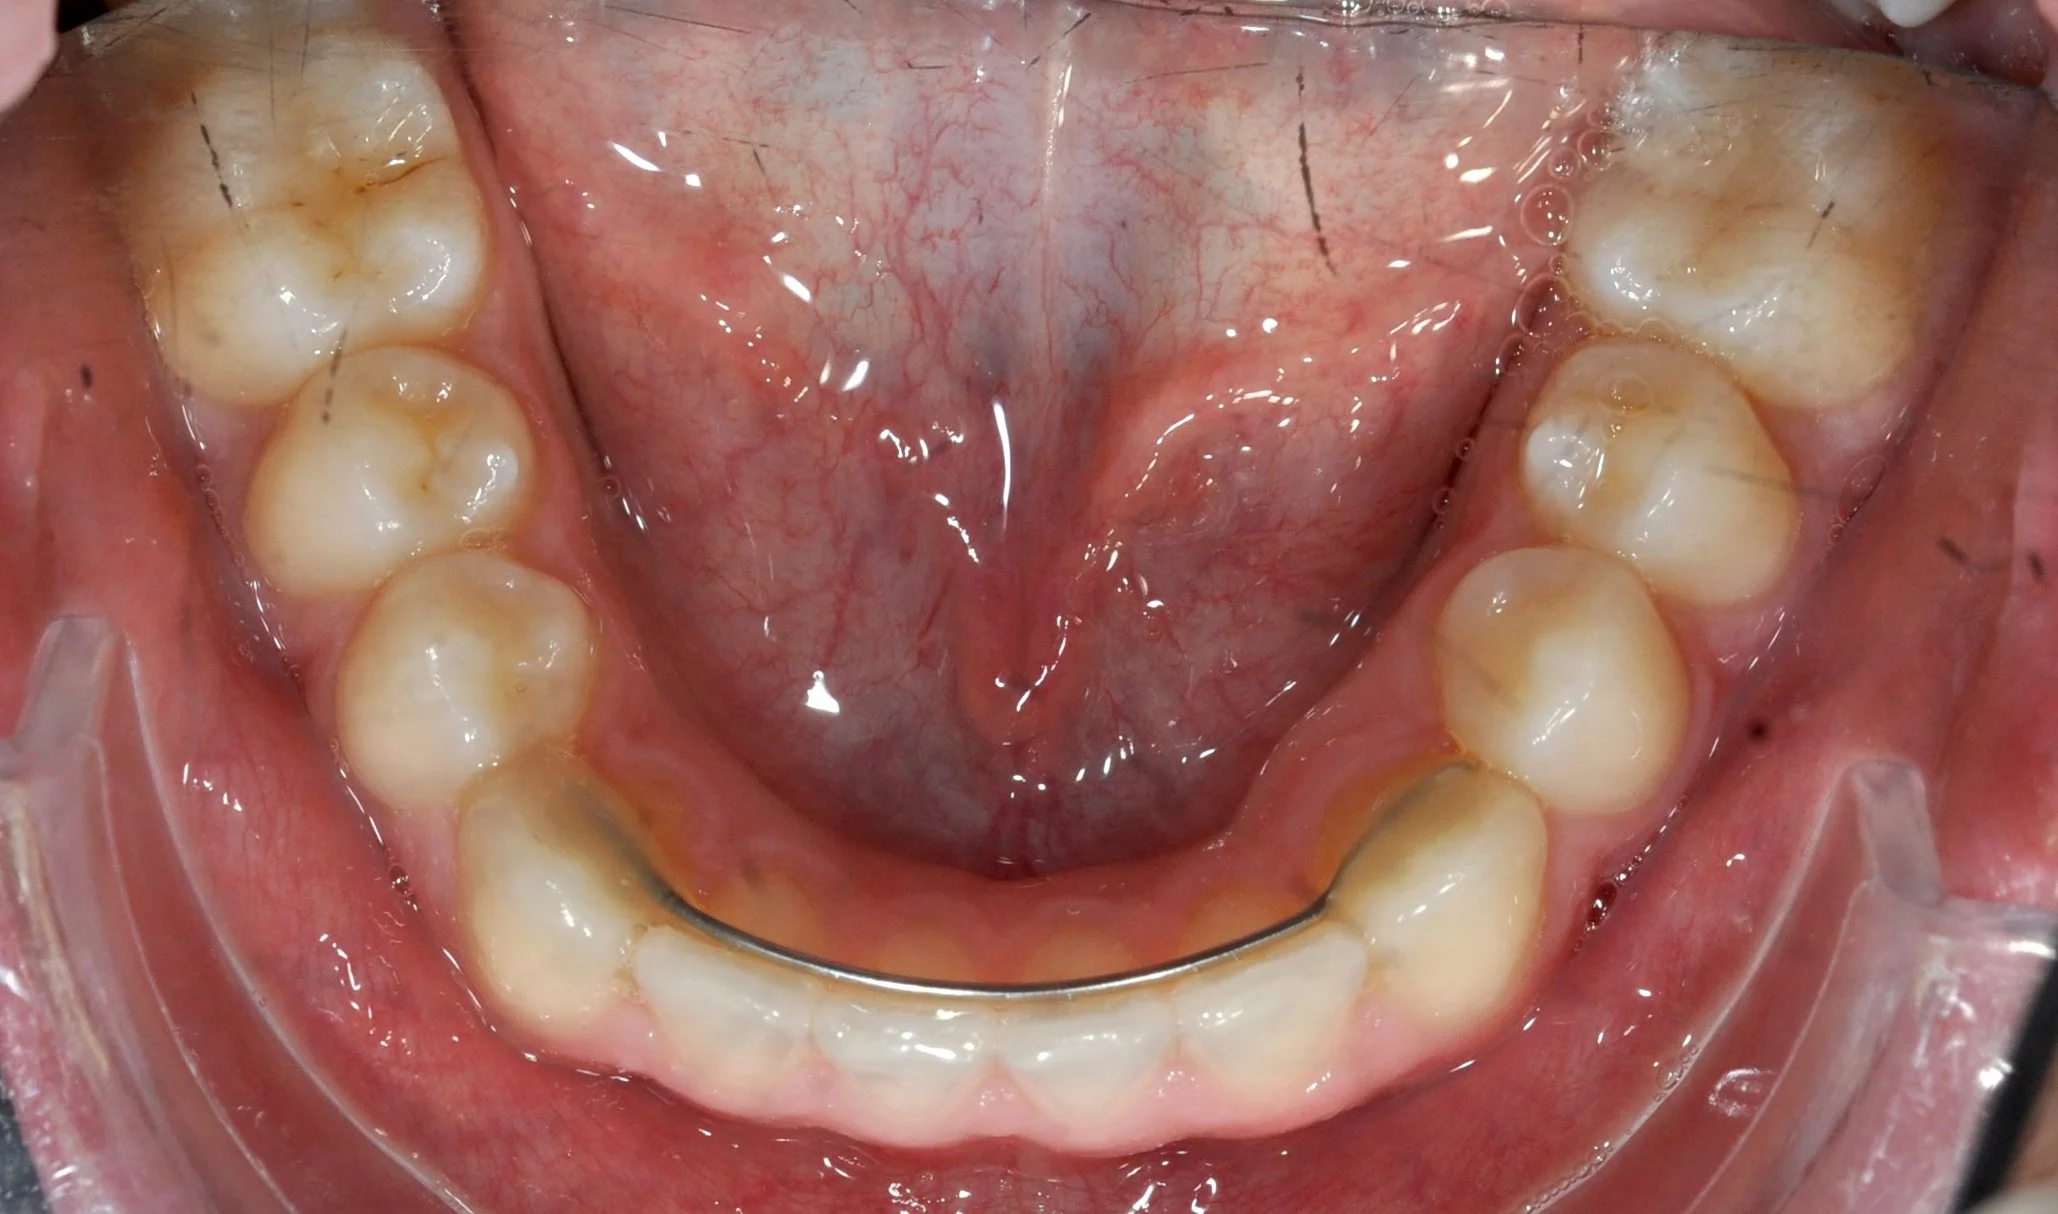

Paziente adulto con importante affollamento dei denti inferiori, arcate strette e tendenza al morso aperto, con difficoltà nel corretto contatto tra i denti superiori e inferiori.

Il trattamento con allineatori trasparenti ha permesso, in circa 18–20 mesi, di riallineare i denti, ampliare le arcate e migliorare la chiusura del morso, ottenendo un risultato stabile, funzionale ed esteticamente armonioso.

PRIMA